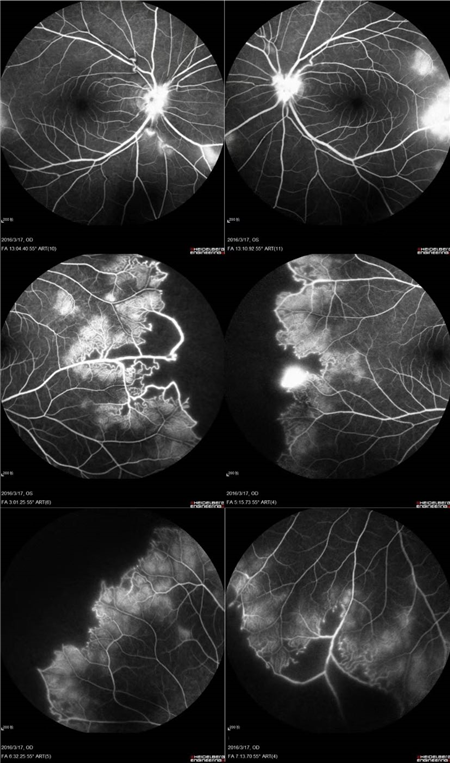

经过详细的眼底检查后,患者被诊断为IRVAN综合征引起的右眼黄斑裂孔,张风院长带领医生团队为患者施局右眼玻璃体切除+剥膜+眼内光凝+气液交换手术,经过半个月的恢复,患者右眼术后视力由术前0.3-达到0.6-的状态,且裂孔呈逐渐闭合状态。

视盘附近的动脉和动脉分叉处出现瘤样动脉扩张,视盘充血,边界不清,引起视盘周围视网膜内硬性渗出;视盘周可有少量放射状出血。

静脉不规则扩张和血管鞘膜,周边部小血管广泛闭塞,交界处毛细血管扩张和异常吻合。

严重者可发生从周边到黄斑的血管闭塞和缺血、玻血、新生血管性青光眼,最终视神经萎缩。